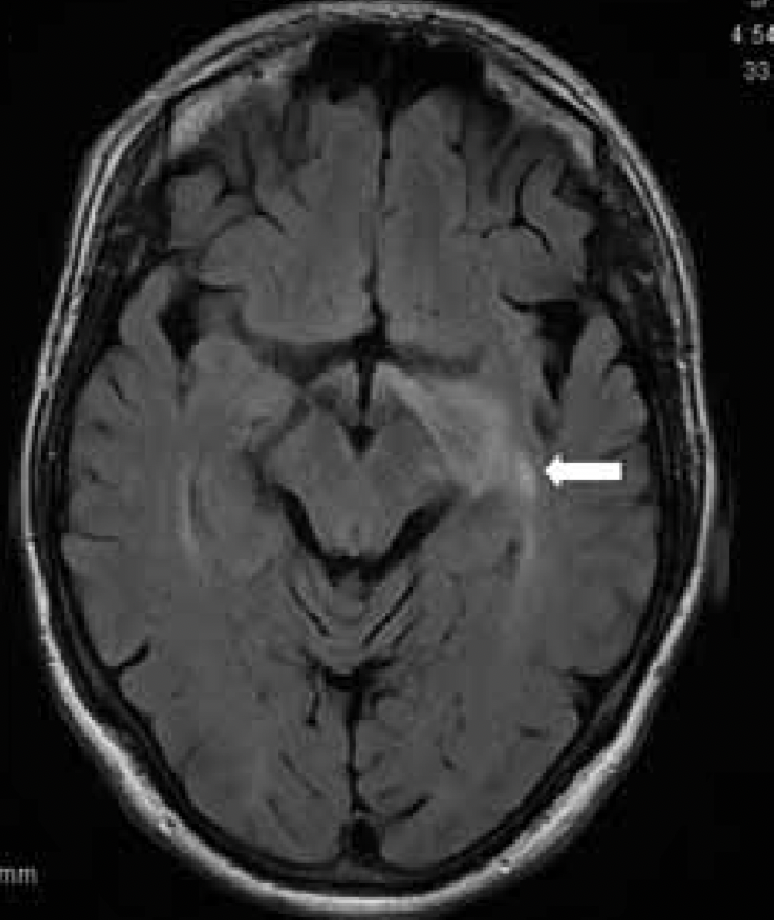

TQ Quiz | Finding the Wolf in Your Visual Field Testing (Sarasota 2025) by Events@optometricedu.com | Mar 9, 2025 | 2025 Sarasota, TQ Courses | 1 comment "*" indicates required fields Step 1 of 2 50% Access CodePlease enter the code provided in the post-event email from OEC to complete your CEE/TQ exam. If you did not receive a code, please email our team at events@optometricedu.com. QuizThis field is hidden when viewing the formDate (Hidden) MM slash DD slash YYYY This field is hidden when viewing the formEvent Date (Hidden) MM slash DD slash YYYY This field is hidden when viewing the formEvent 90 days past date (Hidden) MM slash DD slash YYYY This field is hidden when viewing the formEvent Date Difference (Hidden)1. 65 yo WM with HTN, a-fib on coumadin: acute visual loss, 20/20 OU, no RAPD, normal fundus OU. Which of the following visual field defects is most likely?* A - A B - B C - C D - D 2. 45 yo WM with chronic, progressive visual loss OU, RAPD OS, and optic atrophy OU. Which of the following visual field defects is most likely?* A - A B - B C - C D - D E - E F - F 3. 45 yo AAF with bilateral visual loss, intractable Nasea, Vomitting, and hiccups. Which of the following visual field defects is most likely?* A - A B - B C - C D - D E - E F - F 4. 25 yo WF with worst headache of life. Which of the following visual field defects is most likely?* A - A B - B C - C D - D E - E F - F 5. 55 yo WF with multiple episodes of smelling smoke x 4 with altered mental status. Which of the following visual field defects is most likely?* A - A B - B C - C D - D E - E F - F 6. 55 yo WM with bilateral visual loss. Which of the following visual field defects is most likely?* A - A B - B C - C D - D E - E F - F 7. 45 yo with hyponatremia s/p rapid replacement therapy. Which of the following visual field defects is most likely?* A - A B - B C - C D - D E - E F - F 8. Which of the following visual field defects is most likely in a macroprolactinoma of the pituitary?* A - A B - B C - C D - D E - E F - F 9. Which of the following visual field defects is most likely in a left occipital lobe lesion?* A - A B - B C - C D - D 10. Which of the following visual field defects is most likely in a left temporal lobe lesion* A - A B - B C - C D - D E - E F - F 11. Which of the following visual field defects is most likely in a right optic tract lesion?* A - A B - B C - C D - D E - E F - F 12. Which of the following visual field defects is most likely to be associated with amenorrhea/galatorhhea?* A - A B - B C - C D - D E - E F - F 13. Which of the following visual field defects is most likely to be lateral geniculate body?* A - A B - B C - C D - D E - E F - F 14. Which of the following visual field defects is macular sparing?* A - A B - B C - C D - D E - E F - F 15. Which of the following visual field defects is incongruous?* A - A B - B C - C D - D E - E F - F 16. Which of the following visual field defects is associated with pituitary apoplexy?* A - A B - B C - C D - D E - E F - F 17. Which of the following visual field defects is associated with parietal lobe lesion?* A - A B - B C - C D - D E - E F - F 18. Which of the following visual field defects is associated with the anterior choroidal infarct?* A - A B - B C - C D - D E - E F - F 19. A patient with a visual field defect that is homonymous, has a RAPD and band atrophy of the disc localizes to which area?* A - Optic tract lesion B - Occipital lobe lesion C - Temporal lobe lesion D - Chiasmal lesion 20. A visual field defect that presents as a wedge sectoranopia localizes to which structure?* A - Papillomacular bundle B - Lateral geniculate body C - Parietal lobe D - Temporal lobe Personal InformationName* First Last Email* Phone*OE Tracker #License #Address* Street Address Address Line 2 City State / Province / Region ZIP / Postal Code AfghanistanAlbaniaAlgeriaAmerican SamoaAndorraAngolaAnguillaAntarcticaAntigua and BarbudaArgentinaArmeniaArubaAustraliaAustriaAzerbaijanBahamasBahrainBangladeshBarbadosBelarusBelgiumBelizeBeninBermudaBhutanBoliviaBonaire, Sint Eustatius and SabaBosnia and HerzegovinaBotswanaBouvet IslandBrazilBritish Indian Ocean TerritoryBrunei DarussalamBulgariaBurkina FasoBurundiCabo VerdeCambodiaCameroonCanadaCayman IslandsCentral African RepublicChadChileChinaChristmas IslandCocos IslandsColombiaComorosCongoCongo, Democratic Republic of theCook IslandsCosta RicaCroatiaCubaCuraçaoCyprusCzechiaCôte d'IvoireDenmarkDjiboutiDominicaDominican RepublicEcuadorEgyptEl SalvadorEquatorial GuineaEritreaEstoniaEswatiniEthiopiaFalkland IslandsFaroe IslandsFijiFinlandFranceFrench GuianaFrench PolynesiaFrench Southern TerritoriesGabonGambiaGeorgiaGermanyGhanaGibraltarGreeceGreenlandGrenadaGuadeloupeGuamGuatemalaGuernseyGuineaGuinea-BissauGuyanaHaitiHeard Island and McDonald IslandsHoly SeeHondurasHong KongHungaryIcelandIndiaIndonesiaIranIraqIrelandIsle of ManIsraelItalyJamaicaJapanJerseyJordanKazakhstanKenyaKiribatiKorea, Democratic People's Republic ofKorea, Republic ofKuwaitKyrgyzstanLao People's Democratic RepublicLatviaLebanonLesothoLiberiaLibyaLiechtensteinLithuaniaLuxembourgMacaoMadagascarMalawiMalaysiaMaldivesMaliMaltaMarshall IslandsMartiniqueMauritaniaMauritiusMayotteMexicoMicronesiaMoldovaMonacoMongoliaMontenegroMontserratMoroccoMozambiqueMyanmarNamibiaNauruNepalNetherlandsNew CaledoniaNew ZealandNicaraguaNigerNigeriaNiueNorfolk IslandNorth MacedoniaNorthern Mariana IslandsNorwayOmanPakistanPalauPalestine, State ofPanamaPapua New GuineaParaguayPeruPhilippinesPitcairnPolandPortugalPuerto RicoQatarRomaniaRussian FederationRwandaRéunionSaint BarthélemySaint Helena, Ascension and Tristan da CunhaSaint Kitts and NevisSaint LuciaSaint MartinSaint Pierre and MiquelonSaint Vincent and the GrenadinesSamoaSan MarinoSao Tome and PrincipeSaudi ArabiaSenegalSerbiaSeychellesSierra LeoneSingaporeSint MaartenSlovakiaSloveniaSolomon IslandsSomaliaSouth AfricaSouth Georgia and the South Sandwich IslandsSouth SudanSpainSri LankaSudanSurinameSvalbard and Jan MayenSwedenSwitzerlandSyria Arab RepublicTaiwanTajikistanTanzania, the United Republic ofThailandTimor-LesteTogoTokelauTongaTrinidad and TobagoTunisiaTurkmenistanTurks and Caicos IslandsTuvaluTürkiyeUS Minor Outlying IslandsUgandaUkraineUnited Arab EmiratesUnited KingdomUnited StatesUruguayUzbekistanVanuatuVenezuelaViet NamVirgin Islands, BritishVirgin Islands, U.S.Wallis and FutunaWestern SaharaYemenZambiaZimbabweÅland Islands Country Payment InformationPromotional CodeSarasota 2025 - Finding the Wolf in Your Visual Field Testing |TQ*After 90 days, pricing will increase to $30. Price: (Past 90 Days) Sarasota 2025 - Finding the Wolf in Your Visual Field Testing |TQThis course was presented over 90 days ago. Due to this late submission of TQ, your TQ credit price is $30. Price: Retake Discount Price: Promotional Discount Price: (Past 90 Days) Retake Discount Price: (Past 90 Days) Promotional Discount Price: Credit Card* This field is hidden when viewing the formCourse Information (HIDDEN)This field is hidden when viewing the formCourse Name (HIDDEN)This field is hidden when viewing the formRetake Code (HIDDEN)This field is hidden when viewing the formAccess Code (HIDDEN)This field is hidden when viewing the formQuiz URL (HIDDEN)Do not include ending backslash (aka no .com/)This field is hidden when viewing the formCE Hours 1 Comment Angelina Gavel Rukha on April 16, 2025 at 10:42 am Thank you for a great presentation! Reply Submit a Comment Cancel replyYour email address will not be published. Required fields are marked *Comment * Name * Email * Website